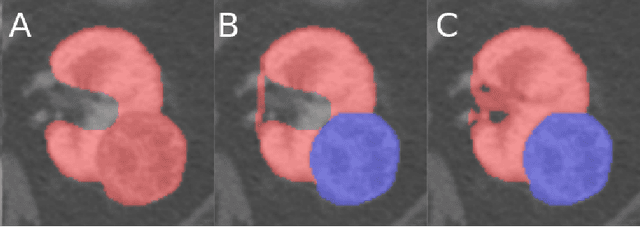

Abstract:This paper presents the challenge report for the 2021 Kidney and Kidney Tumor Segmentation Challenge (KiTS21) held in conjunction with the 2021 international conference on Medical Image Computing and Computer Assisted Interventions (MICCAI). KiTS21 is a sequel to its first edition in 2019, and it features a variety of innovations in how the challenge was designed, in addition to a larger dataset. A novel annotation method was used to collect three separate annotations for each region of interest, and these annotations were performed in a fully transparent setting using a web-based annotation tool. Further, the KiTS21 test set was collected from an outside institution, challenging participants to develop methods that generalize well to new populations. Nonetheless, the top-performing teams achieved a significant improvement over the state of the art set in 2019, and this performance is shown to inch ever closer to human-level performance. An in-depth meta-analysis is presented describing which methods were used and how they faired on the leaderboard, as well as the characteristics of which cases generally saw good performance, and which did not. Overall KiTS21 facilitated a significant advancement in the state of the art in kidney tumor segmentation, and provides useful insights that are applicable to the field of semantic segmentation as a whole.

Abstract:There is a large body of literature linking anatomic and geometric characteristics of kidney tumors to perioperative and oncologic outcomes. Semantic segmentation of these tumors and their host kidneys is a promising tool for quantitatively characterizing these lesions, but its adoption is limited due to the manual effort required to produce high-quality 3D segmentations of these structures. Recently, methods based on deep learning have shown excellent results in automatic 3D segmentation, but they require large datasets for training, and there remains little consensus on which methods perform best. The 2019 Kidney and Kidney Tumor Segmentation challenge (KiTS19) was a competition held in conjunction with the 2019 International Conference on Medical Image Computing and Computer Assisted Intervention (MICCAI) which sought to address these issues and stimulate progress on this automatic segmentation problem. A training set of 210 cross sectional CT images with kidney tumors was publicly released with corresponding semantic segmentation masks. 106 teams from five continents used this data to develop automated systems to predict the true segmentation masks on a test set of 90 CT images for which the corresponding ground truth segmentations were kept private. These predictions were scored and ranked according to their average So rensen-Dice coefficient between the kidney and tumor across all 90 cases. The winning team achieved a Dice of 0.974 for kidney and 0.851 for tumor, approaching the inter-annotator performance on kidney (0.983) but falling short on tumor (0.923). This challenge has now entered an "open leaderboard" phase where it serves as a challenging benchmark in 3D semantic segmentation.

Abstract:The morphometry of a kidney tumor revealed by contrast-enhanced Computed Tomography (CT) imaging is an important factor in clinical decision making surrounding the lesion's diagnosis and treatment. Quantitative study of the relationship between kidney tumor morphology and clinical outcomes is difficult due to data scarcity and the laborious nature of manually quantifying imaging predictors. Automatic semantic segmentation of kidneys and kidney tumors is a promising tool towards automatically quantifying a wide array of morphometric features, but no sizeable annotated dataset is currently available to train models for this task. We present the KiTS19 challenge dataset: A collection of multi-phase CT imaging, segmentation masks, and comprehensive clinical outcomes for 300 patients who underwent nephrectomy for kidney tumors at our center between 2010 and 2018. 210 (70%) of these patients were selected at random as the training set for the 2019 MICCAI KiTS Kidney Tumor Segmentation Challenge and have been released publicly. With the presence of clinical context and surgical outcomes, this data can serve not only for benchmarking semantic segmentation models, but also for developing and studying biomarkers which make use of the imaging and semantic segmentation masks.